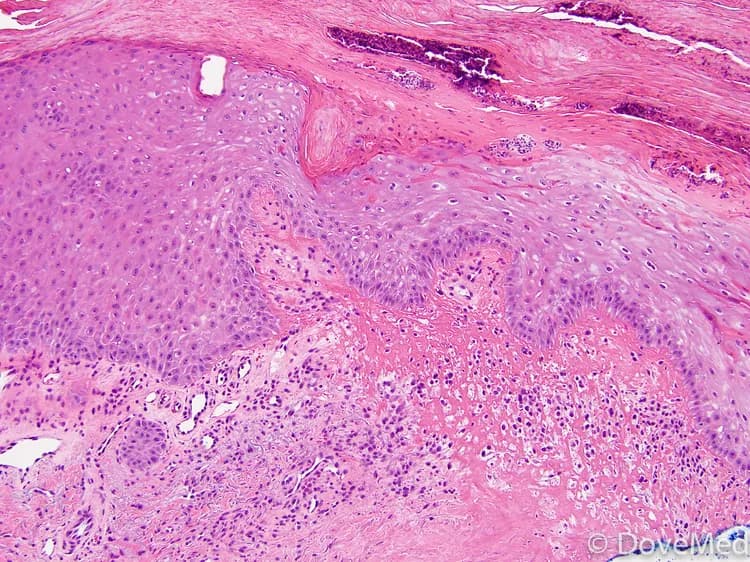

- In situations where the diagnosis is not clear, or if the condition resembles a cancer, then biopsy of the lesion may be required

- Tissue biopsy: In this procedure, the physician removes a sample of the skin tissue and sends it to the laboratory for a histopathological examination. The pathologist examines the biopsy under a microscope and arrives at a definitive diagnosis after a thorough evaluation of the clinical and microscopic findings, as well as by correlating the results of special studies on tissues (if required)

Biopsy of the tissue (from the ear lesion) may identify ulceration in the center and acanthosis and hyperkeratosis in the periphery; granulation tissue may be seen under the ulcer; and vessel proliferation may also be seen.